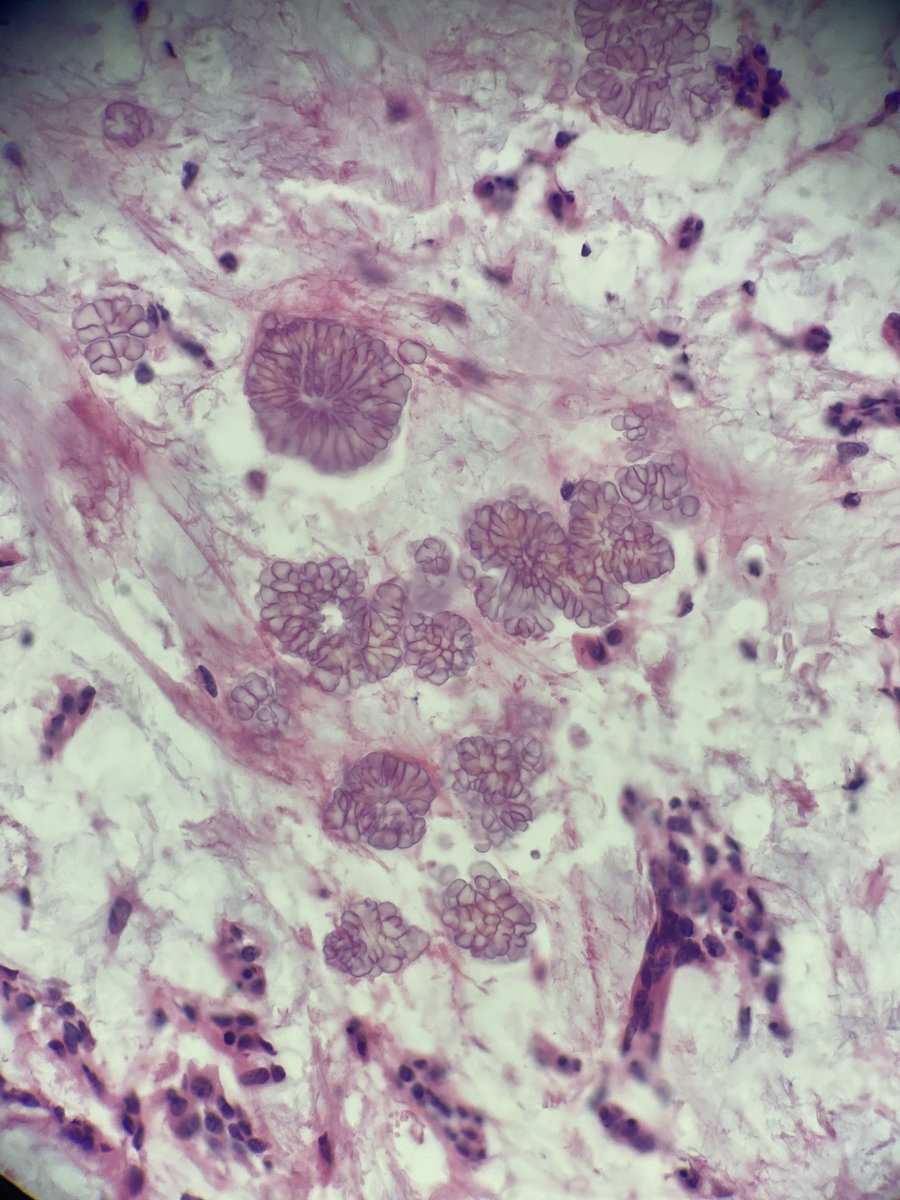

Nasopharyngeal CA (Pics: HP, LP, p40, and EBV ISH).  These can be very tricky as the tumor can be very subtle! Noteworthy feature in this case was the presence of concomitant granulomatous reaction (see PMID 1717637 and 32562216) #PathTwitter #pathology